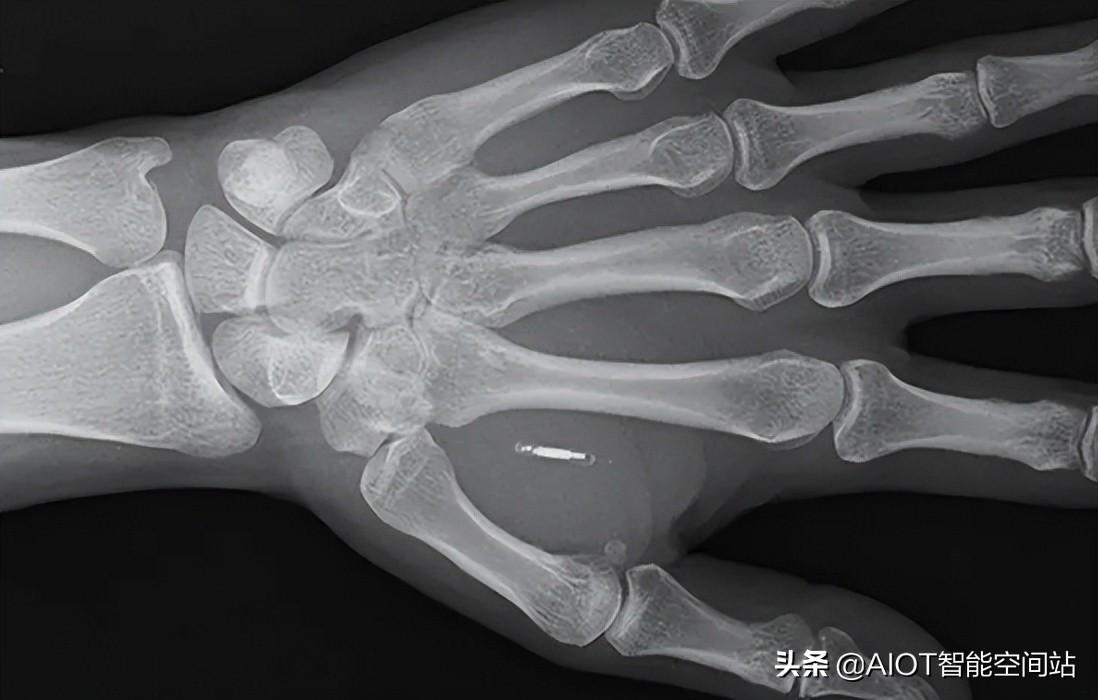

据Walletmor公司介绍,这种植入支付芯片重量不到一克,比一粒米大一点。它是由一个微型芯片和一个天线圈组成,包裹在类似于塑料的天然生物聚合物中。平常感受不到芯片的存在,但在付款的时候,会感觉到像是有人“捏你的皮肤”,并且能感受到手部轻微的震动。芯片植入人体后能立即起作用,并会牢牢固定在原位。此外,它也不需要任何充电装置。